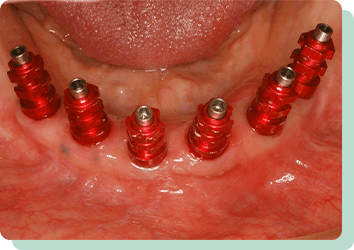

上の歯は残っており、下の歯は全て抜けてしまったケースです。総入れ歯にした場合、受圧加圧のバランスが悪く、何でも噛める入れ歯を作ることは困難です。歯があった時のように食べれるようにという希望でしたが、十分な満足を得ることが出来ました。術後10年以上経過しましたが、問題なく機能しています。

リスク:疼痛・咬合時痛・冷水痛・出血・インプラント手術による歯ぐきなどの損傷・インプラント周囲炎など

費用:インプラントケース総額 2,640,000円